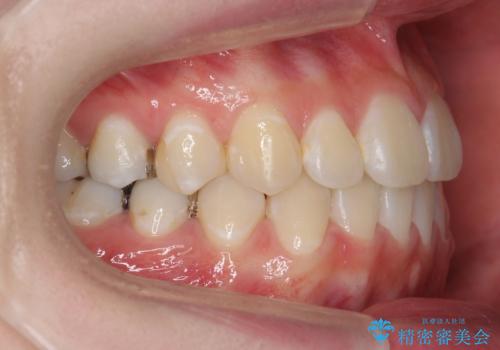

受け口 親知らずを取り込む矯正治療

- 高校生で来院。受け口が主訴でした。

下の小臼歯を抜歯しましたが、その代わり下の親知らずを残して咬ませたので、歯の数は変わっていません。